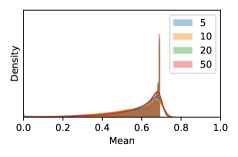

To model how different classifiers will respond to a given input , we assume that the prediction from classifier is sampled from a beta distribution that is characterized by two parameters by and . We further assume that is fixed to the same constant value for all ’s. Under this assumption, each input can be described by ( can be calculated since is fixed), easing further analysis. The Severity Level (SL) of the case represented by image can be characterized by the parameter . The larger the value of , the more severe the case of is. When and are close, the case is ambiguous as the distribution shifts towards being symmetric (i.e. signifying much disagreement among classifiers) rather than being one-sided (i.e. consensus among classifiers that is negative or positive). We provide a set of examples in Figure 2 and also Figure S.8 in the supplementary materials showing how the beta distribution can be used to capture diverse predictions given by an ensemble learner.

We conducted a case study on diagnosing diabetic retinopathy with ensembles of DL models. For benchmarking the performance of our ensemble-based solutions under the scheme described in Sec.3.3, we used two popular collections of diabetic retinopathy image data, the Kaggle Diabetic Retinopathy dataset [22] (hereafter referred to as “Kaggle-DR”) and the Messidor-2 dataset [23], each respectively consisting of and high resolution images. Diabetic retinopathy is graded into five SLs, as displayed in Figure 2. Following the problem setup used in previous papers [24], we trained models to distinguish the referable (SL2-4) cases from the non-referable ones (SL0 & SL1) (see Section B.1 for more detailed descriptions). We also tested our trained ensemble models on two o.o.d. image datasets (ImageNet [25] and CIFAR-10 [26]) to examine their capabilities of identifying o.o.d. inputs (see Section B in the supplementary materials).

In contrast, the MC-dropout method showed the worst overall performance among the three, as it can be seen from the high ratios of SL0 examples among the uncertain negatives in Figure 4. The histograms in Figure 2 provides another perspective to look into the phenomenon, where a decent proportion of MC-dropout model’s predictions on SL0 inputs entailed low confidence (far from 0 or 1), which from another angle explained why MC-dropout was less specific in terms of lower FNP; many no-DR inputs (i.e. SL0) were erroneously assigned high uncertainty by MC-dropout models.

It is still an open question why the evaluated MC-dropout networks signaled relatively high uncertainty on SL0 & SL3 & SL4 data that are less likely to be ambiguous. We conjecture that much of the “uncertainty” indicated by disagreement among test-time dropout samples actually reflects the stochastic nature of dropout networks rather than the real decision uncertainty associated with the data. It is worth noting that the MC-dropout model we evaluated was not weak per se; they all achieved above Area Under Curve (AUC) scores on test sets. The weakness of individual test-time samples (which explains their low-confidence predictions on SL0 & SL3 & SL4) might have been hidden when they are aggregated into an ensemble—a well-known advantage of ensemble learning. Our results suggested that the uncertainty information given by implicit ensemble methods such as MC-dropout and TTA might not be as reliable as that from explicit ensemble approaches (e.g., stacking ensembles). Similar findings on MC-dropout can be found in some previous papers [1].